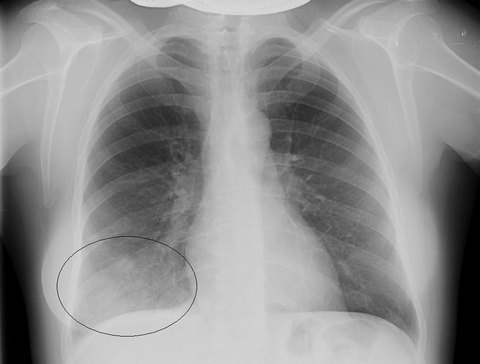

Рентгенограмма лёгких при сегментарной пневмонии

Диагностические предположения подтверждаются на основании данных рентгенографии легких: на снимках выявляются гомогенные интенсивные тени в форме треугольника, имеющие четко очерченные границы, снижение структурности корня. Иногда сегментарную пневмонию удается выявить только при динамическом исследовании, когда появляется ателектатический компонент, придающий границам поражения характерную четкость. В периферической крови определяются острые воспалительные изменения, включающие лейкоцитоз, сдвиг формулы влево повышение СОЭ, наклонность к анемии.